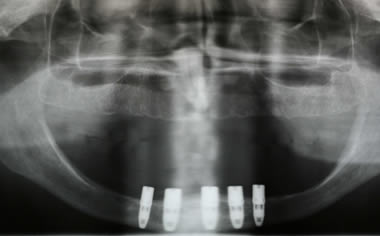

Full arches of teeth replaced by dental implants

Case One (5 images)

Full set of lower teeth fixed onto five dental implants.